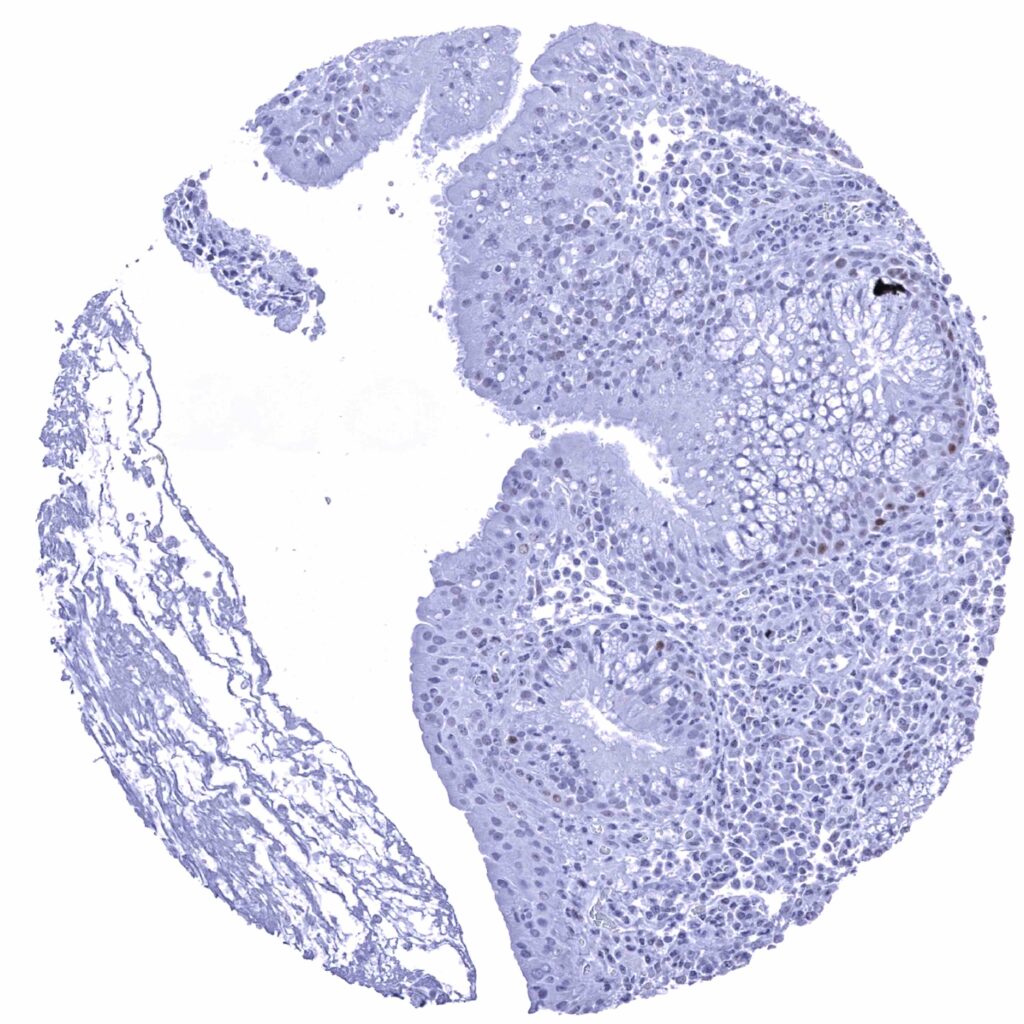

Tonsil – Weak nuclear p53 staining of a fraction of basal and suprabasal cells of the crypt epithelium (p53 immunohistochemistry). Very faint staining of some germinal centre lymphocytes.

Tonsil, surface epithelium – Faint nuclear p53 staining of a fraction of basal and suprabasal cells (p53 immunohistochemistry)